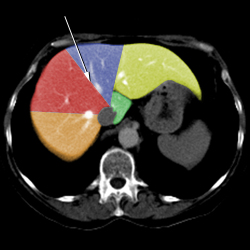

Liver anatomy

Liver lobectomy

Segmental Anatomy of Liver